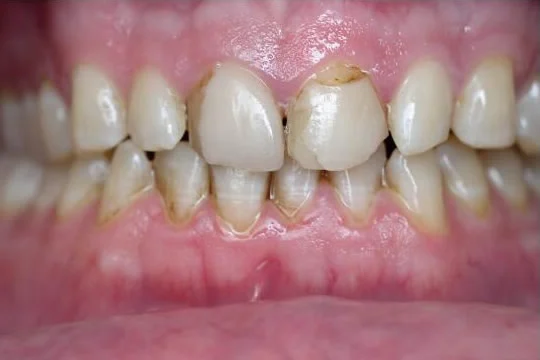

Dr. Halabo’s work reversed 40 years of deterioration and the result made my smile look 40 years younger.

“When I first started coming to your office my smile and self-confidence were less than wonderful. You truly work miracles with the magic that you do. Dr. Halabo, you truly are a phenomenal dentist and person.”

Thanks Dr. Halabo for the great smile… I knew you and your staff would take care of everything to make my smile great. I smile so much more now!